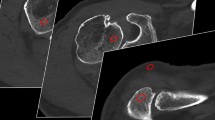

Image quality comparison between a low pitch/slow gantry rotation (P7) and high pitch/fast gantry rotation (P3) protocol in a pelvic photon-counting CT scan. Scan duration (P7: 35.6 vs. P3: 3.8 s) and raw data file size (191.4 vs. 12.8 GByte) differed substantially, whereas CTDIvol was identical (5.83 vs. 5.83 mGy).

To account for differences in signal characteristics, image noise in subcutaneous lipid tissue was compared among scan protocols. The highest noise level was recorded for the high-pitch/fast rotation protocol P3 (159.1 ± 16.6 HU), while the noise magnitude was lowest in the low-pitch/slow rotation protocol P7 (85.1 ± 10.4 HU). The image noise ascertained in P3 was considerably higher than in all three scan protocols with a gantry rotation time of 1 s (P7–9; p ≤ 0.017). Apart from P4 (104.1 ± 16.5 HU; p = 0.120), the image noise measured in P7 was substantially lower than in all other scan protocols (p ≤ 0.027), despite comparable radiation dose. Noise measurements and subjective image quality ratings are summarized in Table 3. Figure 3 illustrates a comparison between the noise level of high pitch/fast rotation (P3) vs. low pitch/slow rotation protocols (P7) in the presence of different metal implants.

Image noise increases considerably when combining a high pitch factor with fast gantry rotation time (P3). This effect becomes even more apparent in the presence of metal artifacts. In contrast, employing a low pitch factor with slow gantry rotation time (P7) partially offset the noise increase in a cadaveric specimen with upper leg osteosynthesis (upper row), while basically removing the streak artifacts in a body donor with dental implants (lower row).